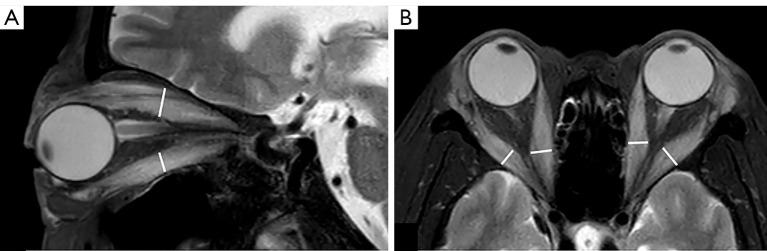

When quantitative magnetic resonance imaging (MRI) is used to assess the activity of Graves' orbitopathy (GO), the examination is generally focused on a specific orbital tissue, especially the extraocular muscles (EOMs). However, GO usually involves the entire intraorbital soft tissue. The aim of this study was to use multiparameter MRI on multiple orbital tissues to distinguish the active and inactive GO.

METHODS

From May 2021 to March 2022, consecutive patients with GO were prospectively enrolled at Peking University People's Hospital (Beijing, China) and divided into those with active disease and those with inactive disease based on a clinical activity score. Patients then underwent MRI, including sequences of conventional imaging, T1 mapping, T2 mapping, and mDIXON Quant. Width, T2 signal intensity ratio (SIR), T1 values, T2 values, and fat fraction of EOMs, as well as water fraction (WF) of orbital fat (OF), were measured. Parameters were compared between the 2 groups, and a combined diagnostic model was constructed using logistic regression analysis. Receiver operating characteristic analysis was used to test the diagnostic performance of the model.

RESULTS

Sixty-eight patients with GO (27 with active GO, 41 with inactive GO) were included in the study. The active GO group had higher values of EOM thickness, T2 SIR, and T2 values, as well as higher WF of OF. The diagnostic model, which included EOM T2 value and WF of OF, demonstrated a good ability to distinguish between active and inactive GO (area under the curve, 0.878; 95% CI: 0.776-0.945; sensitivity, 88.89%; specificity, 75.61%).

CONCLUSIONS

A combined model incorporating the T2 value of EOMs and the WF of OF was able to identify cases of active GO, potentially offering an effective and noninvasive method to assess pathological changes in this disease.